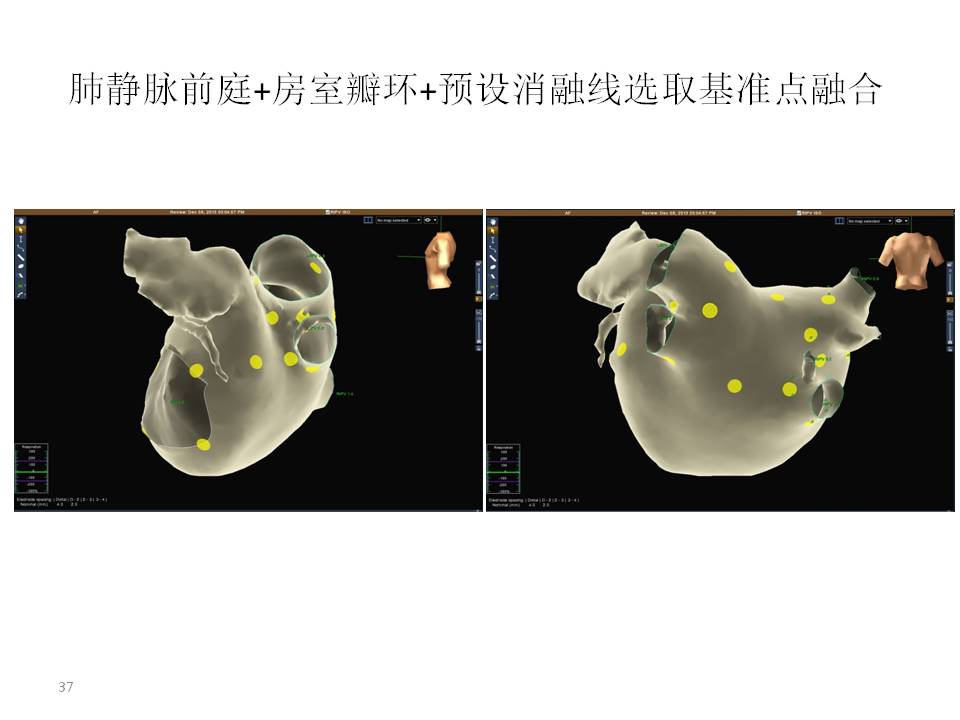

动态融合 实时准确